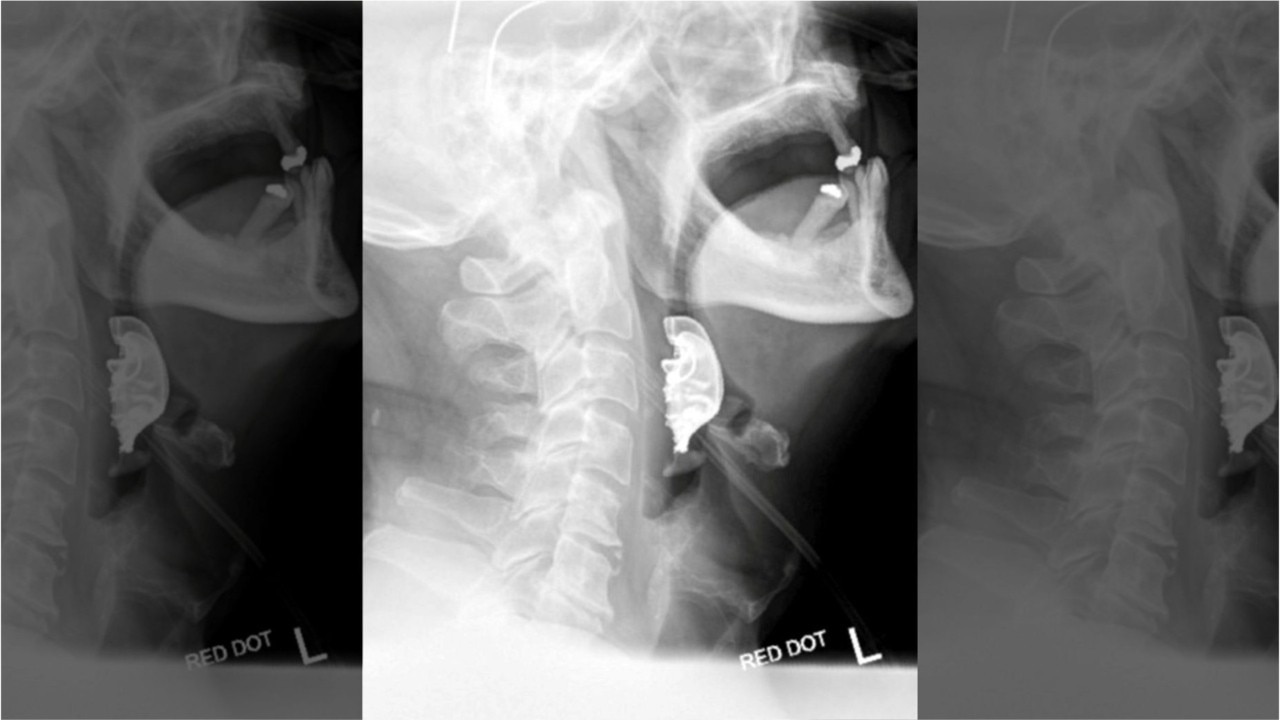

Man undergoes emergency surgery after dentures found lodged in throat days after procedure

A 72-year-old British man?s?dentures?were found lodged in his throat eight days after he had surgery, leading to complications and forcing him to later undergo an emergency procedure.